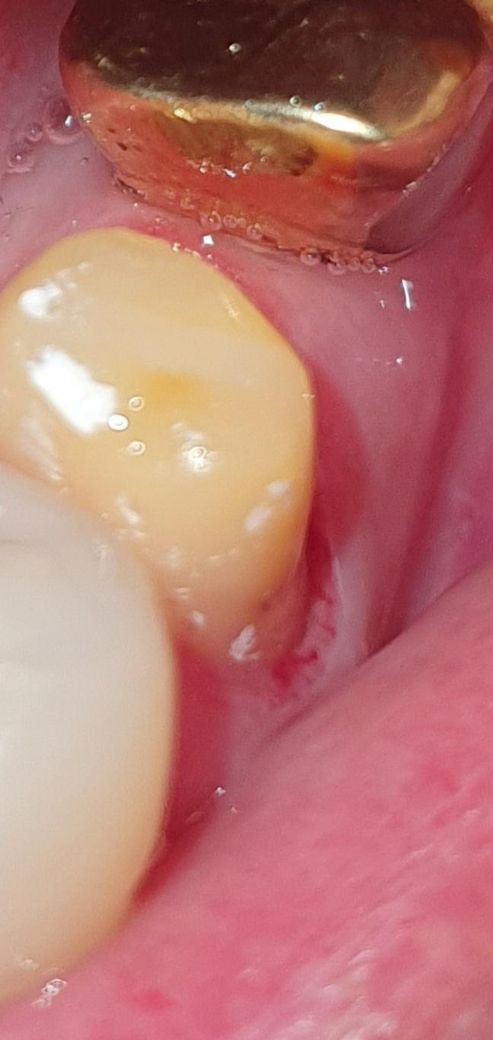

치과 크라운 있던거 벗기고 새로 하면서 잇몸을 절개

기존 크라운 있던거 벗기고 새로 크라운 씌우면서 잇몸을 절개 한 티가 확실히 나는데 치과에서는 잇몸 절개한게 아니라고 하네요 치관확장술 의심 되는데도 사진 보여줬는데도 절개한 사실이 없다고 하는군요 이 시술명이 무엇인지 아시는분 답변 부탁드립니다

잇몸을 절개한건 아니고 치아를 삭제하면서 잇몸도 같이 모양을 만든겁니다. 치은절제나 치관확장술은 아닙니다.

높이확장을 위해 치은절제술, clp(치관확장술) 할수 있고 사진은 치은절제술을 한것이거나 본 잘 뜨려고 치은압배로 잇몸을 좀 벌려놓은 모양새이나 병원에서 안했다면 안하지 않았을까 싶은데요